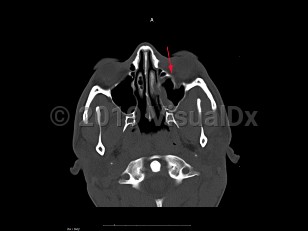

Blow-out fracture of orbit - External and Internal Eye

After sustaining a blunt force injury with an object larger in size than the globe, such as a fist or ball, the orbit is at risk of a "blow-out fracture." Although the lamina papyracea is the thinnest bone of the orbit, the orbital floor is the most common type of orbital fracture. This type of fracture tends to occur just behind the orbital rim but may involve the rim itself.

Patients often present with pain and tenderness to the periorbital region, which may worsen on attempted upgaze. They may note diplopia if there is limited motility of the involved eye. Signs of orbital floor blow-out fracture may include ecchymosis, enophthalmos, hypesthesia of the cheek, crepitus, and restricted eye movements, particularly in upgaze.

As the swelling decreases with time after the trauma, enophthalmos becomes more apparent in larger fractures. In many orbital fractures, swelling and ecchymosis are the only signs.